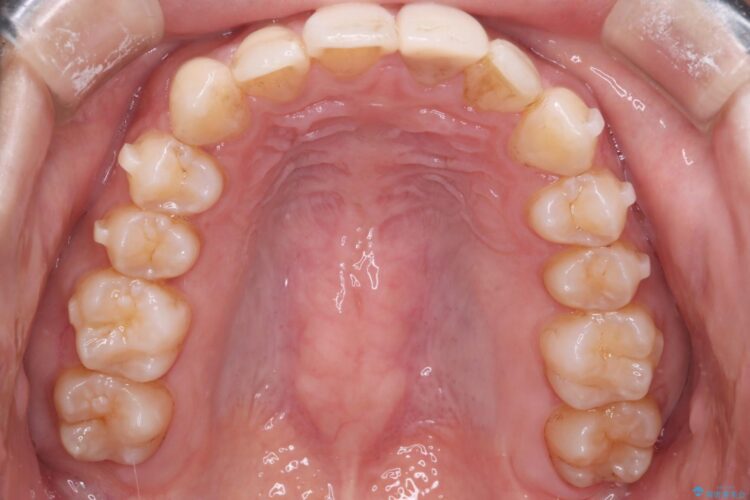

前歯の叢生と口元を下げたいとのことでご来院されました。

骨格的な左右差があるため、正中を合わせることや、抜歯による大幅な口元の変化は難しい旨をご説明し、ご理解いただきました。

その上で今回は抜歯を行わず、歯の表面をわずかに整えるIPRを活用しながら、インビザラインで前歯のガタつきを優先的に改善していく計画を立案しました。